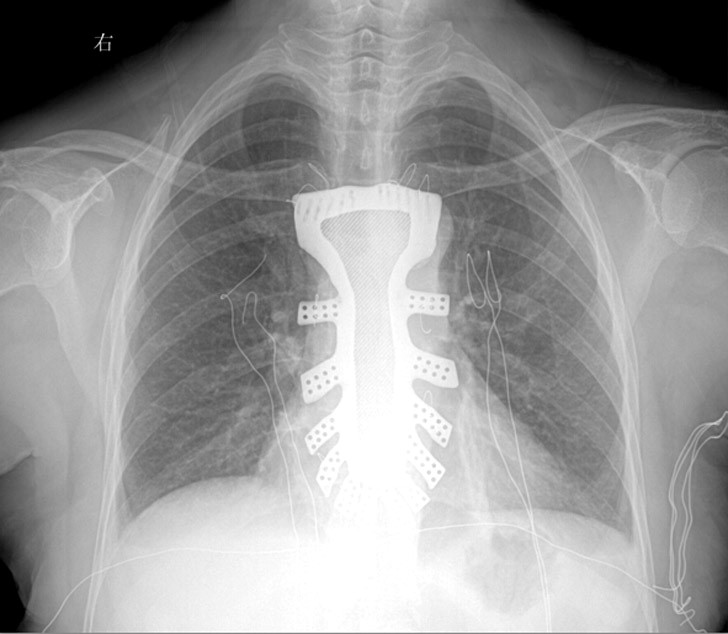

6月22日,该团队收到钛合金植入体之后马上准备手术,这张图片是植入后的情形。顾女士已经恢复,且无任何并发症,我们祝福她。